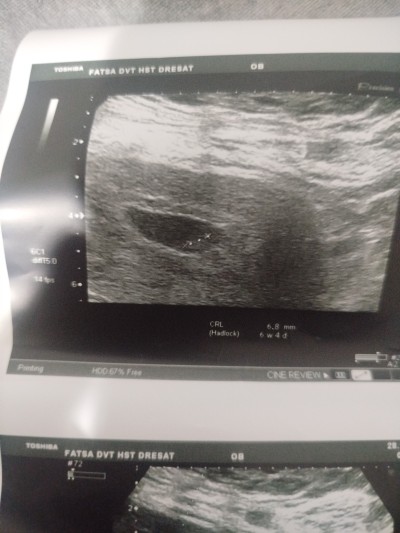

kese şeklıne gore cinsiyet tahmini ne ola bilir

Gebelik haftası 7+4

Bence erkek. Kese yuvarlaksa kız yayvansa erkek diyorlar. Hayırlısı olsun sağlıkla gelsin inşallah 🙏

Bu teori çok yanlış dontorlar açıklıyor keseye göre cinsiyet belirlenmez benim ultrason fotoğrafları kimi yuvarlak kimi fasulye gibiydi doktorun hangi açıdan tutmasına bağlı olarak değişiyor

Keseye göre erkek ama bebeğin olduğu yere göre kız